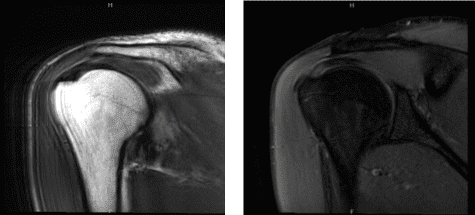

MRI were reviewed and discussed; Acromioclavicular Joint: The undersurface of the acromion is curved. There is mild acromioclavicular joint arthrosis. Rotator Cuff: There is a partial-thickness tearing the superior subscapularis tendon. There is tendinosis in the supraspinatus tendon.

The infraspinatus, and teres minor tendons are intact. There is no disproportionate muscle atrophy. The rotator interval is normal. Biceps And Labrum: The long head of the biceps’ tendon is intact and maintained in the bicipital groove. The labrum and biceps labral anchor are intact. Glenohumeral Joint:

There is a physiologic amount of fluid within the joint. The articular cartilage is maintained. Bones: There is no acute fracture or osteonecrosis. There is no suspicious bone marrow edema. Bursae: There is no significant subacromial-subdeltoid bursitis.

Miscellaneous: The deltoid muscle is maintained. There is no significant axillary lymphadenopathy. The subcutaneous tissues are within normal limits. Which means the shoulder’s MRI showed that there is a rotator cuff tear along with acromial spur and AC arthritis of the right shoulder.

MRI Right shoulder non-contrast